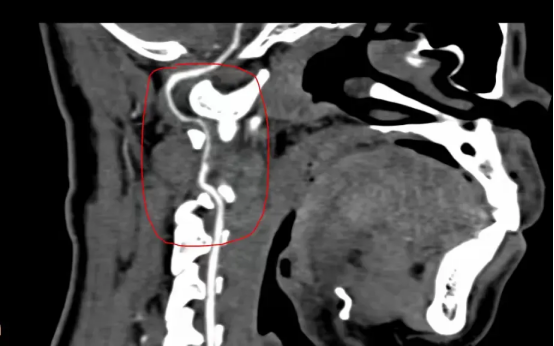

图为患者的头颈联合CTA,考虑左椎动脉V3段夹层伴附壁血栓形成

为进一步明确夹层的位置、长度以及血流情况并进一步治疗,脑五科团队为患者进行脑血管造影检查明确为椎动脉夹层,血流良好,不需要血管内治疗。经积极抗凝等治疗,宋先生头晕及双下肢无力等症状基本消失。